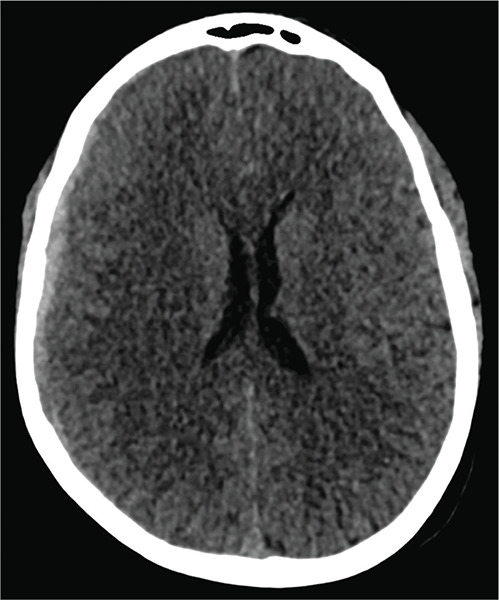

Teaching point: Although computed tomography (CT) is the diagnostic gold standard for acute subdural hematoma, the absence of clear trauma should prompt the use of computed tomography angiography (CTA) to identify potential underlying causes, such as ruptured aneurysms, which can significantly influence treatment decisions.

教学要点:虽然计算机断层扫描(CT)是诊断急性硬膜下血肿的金标准,但如果没有明确的外伤,则应立即使用计算机断层扫描血管造影术(CTA)来识别潜在的潜在病因,如动脉瘤破裂,这对治疗决策有重大影响。